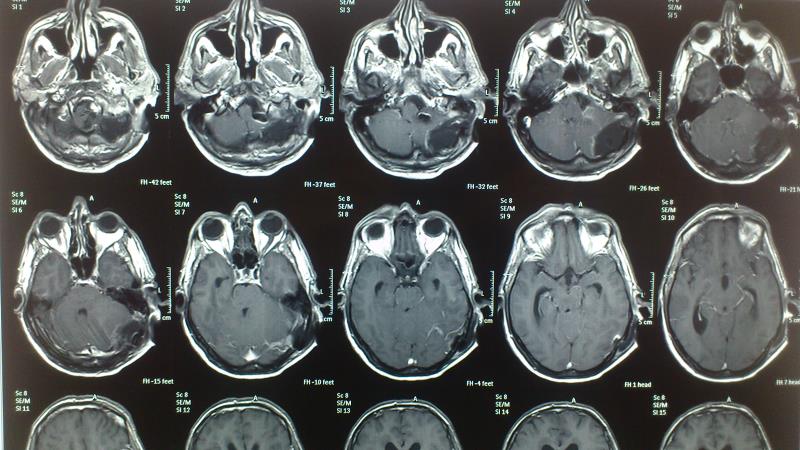

Ασθενής  άνδρας 55 ετών  προσήλθε λόγω αστάθειας βάδισης  και πάρεσης  των κατώτερων εγκεφαλικών συζυγιών  ( ΙΧ,Χ,ΧΙ ). Ο  έλεγχος με μαγνητική τομογραφία εγκεφάλου ανέδειξε εικόνα συμβατή  με μηνιγγίωμα ινιακού τρήματος με σημαντική πίεση επί του στελέχους. Ο ασθενής υποβλήθηκε σε αριστερή  Far Lateral Transcondylar προσπέλαση. Μετεγχειρητικά ο ασθενής παρουσίασε ήπια επιδείνωση της πάρεσης των κατώτερων εγκεφαλικών συζυγιών που ωστόσο αποκαταστάθηκε σταδιακά στα προεγχειρητικά επίπεδα Ο μετεγχειρητικός απεικονιστικός έλεγχος ανέδειξε ολική αφαίρεση του όγκου.

Προεγχειρητικός απεικονιστικός έλεγχος